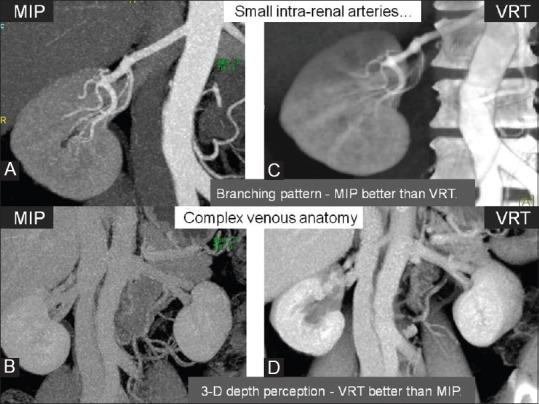

As Laparoscopic Donor Nephrectomy (LDN) offers several advantages for the donor such as lesser post-operative pain, fewer cosmetic concerns and faster recovery time, there is growing global trend towards LDN as compared to open nephrectomy. Comprehensive pre-LDN donor evaluation includes assessment of renal morphology including pelvi-calyceal and vascular system. Apart from donor selection, evaluation of the regional anatomy allows precise surgical planning. Due to limited visualization during laparoscopic renal harvesting, detailed pre-transplant evaluation of regional anatomy, including the renal venous anatomy is of utmost importance. MDCT is the modality of choice for pre-LDN evaluation of potential renal donors. Apart from appropriate scan protocol and post-processing methods, detailed understanding of surgical techniques is essential for the Radiologist for accurate image interpretation during pre-LDN MDCT evaluation of potential renal donors. This review article describes MDCT evaluation of potential living renal donor, prior to LDN with emphasis on scan protocol, post-processing methods and image interpretation. The article laid special emphasis on surgical perspectives of pre-LDN MDCT evaluation and addresses important points which transplant surgeons want to know.